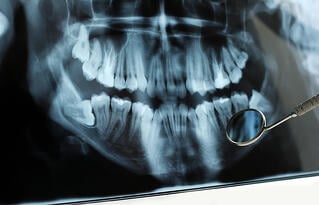

Singapore oral and maxillofacial surgeons perform orthognathic surgery, also commonly known as corrective jaw surgery, to treat problems caused by uneven jaw development or abnormal jaw positioning. Jaw surgery is considered a safe and effective procedure due to its low rates of serious complications. However, it is important that Singapore patients are aware that there are risks involved with the surgery, as is the case with any surgical procedure. Knowing the risks of the procedure, weighing them against its benefits and discussing your concerns with your Singapore oral surgeon is essential to making solid, well-informed decisions about your care.

Among the most common conditions treated with jaw surgery are occlusion issues caused by uneven or misaligned jaws, such as severe overbite, underbite, cross bite or open bite. All of these conditions can cause functional problems, including poor biting and chewing efficiency, abnormal tooth wear, speech impediments and breathing difficulties, as well as the aesthetic issues, such as chin protrusion or recession, an inability to close the mouth naturally or unbalanced facial features. Correcting overbite or other jaw position and/or size via orthognathic surgery can resolve both functional and aesthetic issues caused by these conditions, improving a patient's quality-of-life.